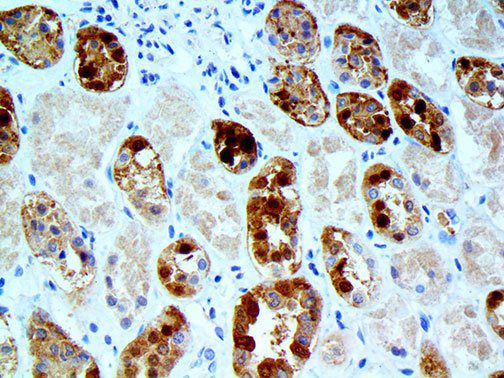

The first cytokines released are interleukin 1β (IL-1β) and tumor necrosis factor-α (TNF-α), which attract a variety of circulating white blood cells (WBCs) to the infection site, including neutrophils, monocytes, macrophages, and natural killer (NK) cells. This response, along with the antipathogenic chemicals released by these cells (i.e., complement), comprise the innate immune response. These cells directly attack the invading pathogen and also release additional cytokines, chief among them interleukin-1 and 6 (IL-6). IL-6 is essential for invoking the adaptive immune response, which calls T-cells, B-cells, and T helper (Th) cells to the infection site. IL-6 also stimulates further recruitment, proliferation and activation of macrophages.

It is the ICU physician who is most likely to witness one of the deadliest manifestations of the abnormal immunological response, the cytokine storm syndrome (CSS). This response is also referred to by some as the cytokine release syndrome (CRS). CSS is characterized by continuous activation and expansion of macrophage and lymphocyte populations, which secrete large amounts of cytokines, causing the cytokine storm. This massive cytokine release is akin to hemophagocytic lymphohistiocytosis (HLH) disease, a syndrome characterized by initial unchecked and persistent activation of cytotoxic T lymphocytes and NK cells.

This activation induces inflammatory monocytes to highly express IL-6, starting a localized and then systemic cascade effect that results in hyperproduction of IL-6, which accelerates the inflammatory process. Because IL-6 also increases vascular permeability, excessive levels cause blood vessels to become very leaky. This, along with clotting factors released from vascular endothelial cells, stimulates the coagulation cascade, resulting in microthrombosis (tiny clots), which leads to ischemia and tissue death of the kidney, intestines, heart, liver, brain and extremities.